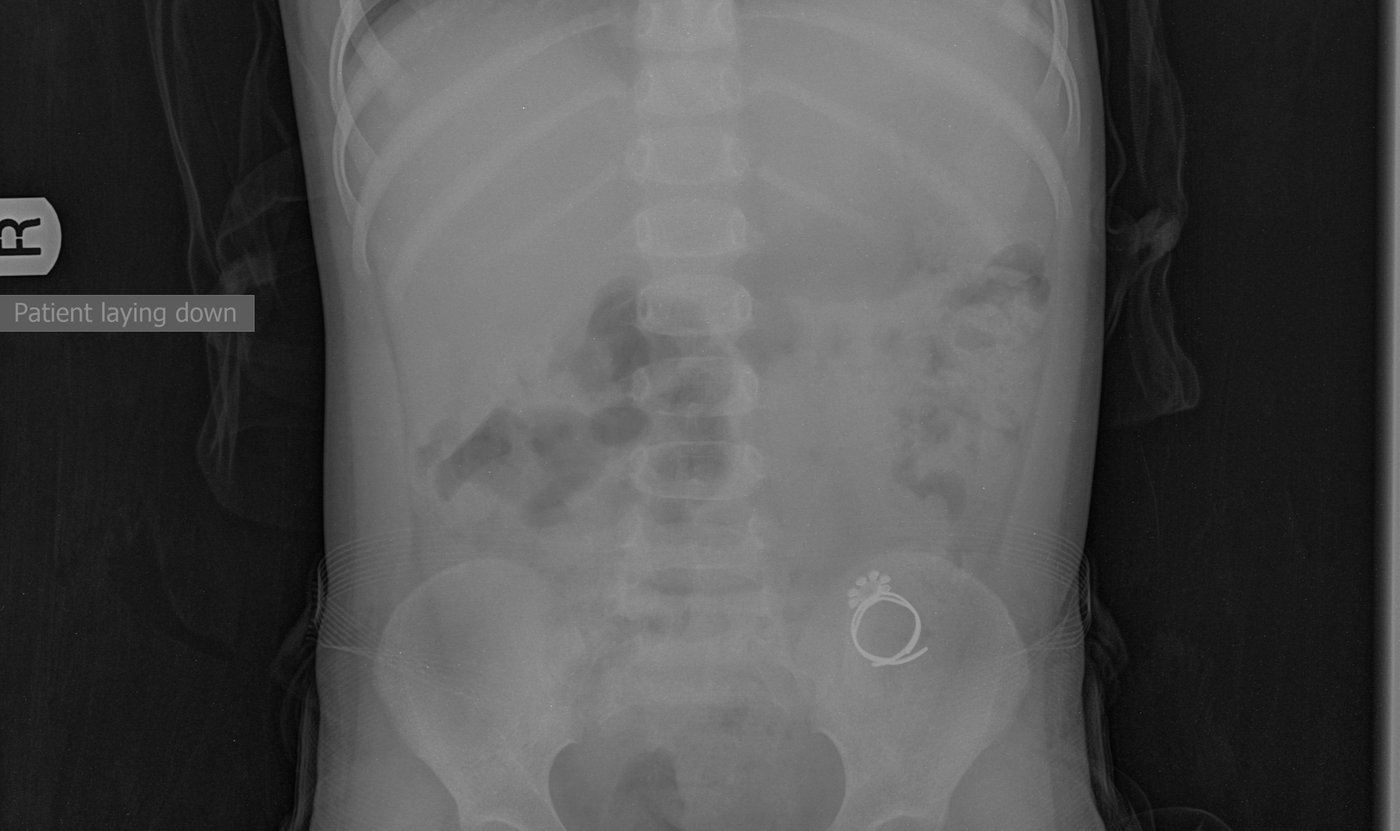

"רות הקטנה שלנו בלעה טבעת ונחנקה", מספרים בני המשפחה ל'כיכר השבת', "הטבעת, בצד אחד היתה חדה כסכין [ניתן לראות בתמונה] ויכלה לגרום לנזקים בלתי הפיכים. ה' יתברך ריחם עלינו ובחסדי שמים גדולים הטבעת ירדה לקיבה ויצאה בצורה טבעית".